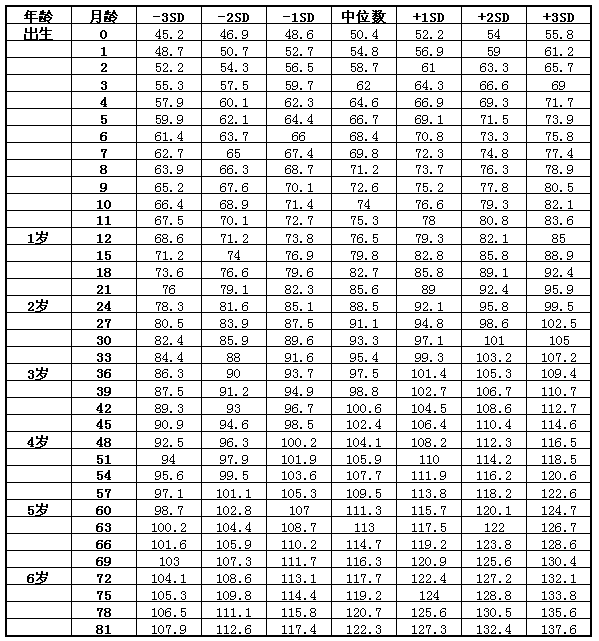

關(guān)于七個(gè)月寶寶的發(fā)育標(biāo)準(zhǔn)表,全方位了解寶寶成長里程碑,七個(gè)月寶寶發(fā)育標(biāo)準(zhǔn)表全解析,寶寶成長里程碑一覽

摘要:本文介紹了關(guān)于七個(gè)月寶寶發(fā)育的標(biāo)準(zhǔn)表,全方位展示了寶寶成長的里程碑。內(nèi)容包括寶寶在這個(gè)階段的身體發(fā)育、動(dòng)作發(fā)展、語言能力、社交能力等方面的表現(xiàn)。通過這份摘要,家長們可以更加清晰地了解寶寶在這個(gè)階段的發(fā)展?fàn)顩r,為...